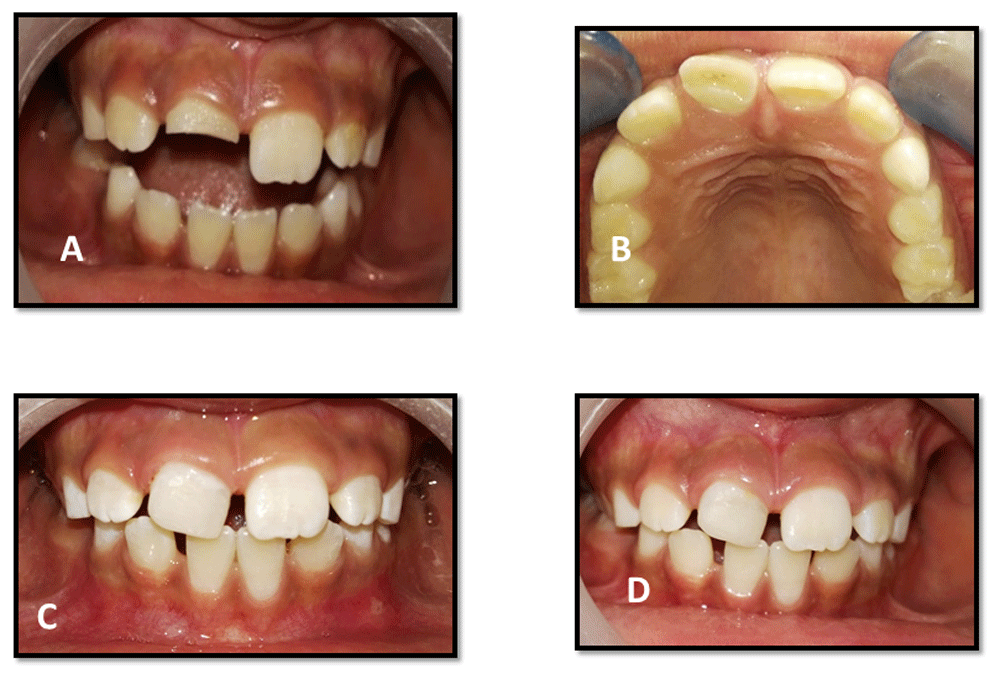

An 8.5-year-old Egyptian girl came to the outpatient clinic of Pediatric Dentistry and Dental Public Health Department, Faculty of Dentistry, Cairo University with the chief complaint of fractured upper right central incisor due to trauma one and half months previously (Figure 1A and B). The patient’s medical history was non-contributory. On clinical examination (which included a visual examination for any abnormalities, palpation of labial vestibule, percussion test and sensibility test), the tooth was sensitive to percussion, which was determined by tapping the tooth with the back of the mirror. The surrounding soft tissue had no tenderness to finger palpation and the tooth had no response to the hot test in comparison to the contralateral tooth. Preoperative radiographic examination revealed a wide root canal with an open apex (Figure 2A) using conventional periapical radiograph.

A) front view of preoperative intra-oral photo of traumatized upper right central incisor; B) occlusal preoperative photo; C) three month follow up; and D) 12-month follow-up.

Clinical examination of the patient revealed no adverse signs and symptoms at three, six-, nine- and 12-month follow-up periods (Figure 1C and 1D). Radiographic examination revealed an increase in root length and root thickness at six months (Figure 2C) and complete root closure at 12 months (Figure 2D) using digital radiography (Digora™ Optime UV) and digital software (Soredex, Finland). (Table 1)